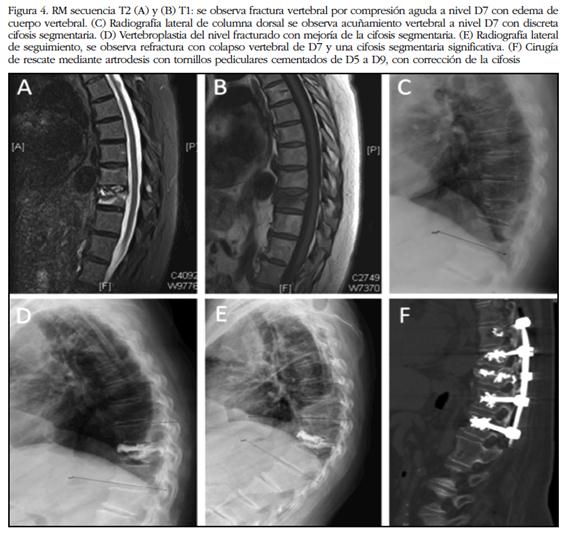

La vertebroplastia y la cifoplastia son procedimientos terapéuticos que pueden incluirse dentro de las denominadas “técnicas de refuerzo vertebral” y que son llevados a cabo por radiólogos intervencionistas, por traumatólogos o por neurocirujanos, de forma percutánea habitualmente con abordaje transpedicular. La vertebroplastia percutánea consiste en la introducción de un cemento óseo, que puede ser el polimetilmetacrilato (PMMA), en un cuerpo vertebral fracturado, para aliviar el dolor mediante el refuerzo y la estabilización de la fractura vertebral (Figura 4). De forma similar a la vertebroplastia, en la cifoplastia percutánea, previamente a la administración del cemento a nivel de la vértebra fracturada, se inserta un balón que se insufla, con la finalidad de restaurar la altura del cuerpo vertebral y reducir la deformidad cifótica; al retirar el balón, permanece en el interior del cuerpo vertebral una cavidad o nido que permite introducir el cemento a menor presión y con mayor viscosidad, con lo que se reduce el riesgo de extravasación. Algunos autores prefieren denominar la cifoplastia como "vertebroplastia mediante balón" 53.